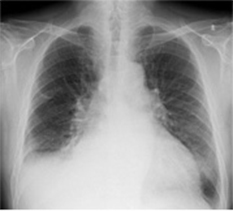

定期健康診断で検出された症例です。経時差分画像により、肺野外の病変異常に対しても変化を把握し易くなります。

正常患者を正常と言い切るのは診療上勇気がいるため、異常画像より読影時間がかかるという報告があります。経時差分の導入により、確信度が上昇し、読影時間を短縮できます。